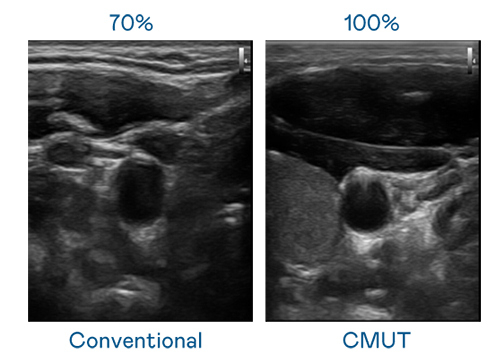

CMUT 技术是一种用电容式微机电元件来产生超音波讯号的技术。与传统 PZT 压电式技术相比,CMUT 频宽增加 30%,更宽频的超音波讯号让影像解析度大幅提升,是实现高影像品质医疗超音波扫描、促进精准医疗发展的关键技术。

大频宽带来超清晰影像

超音波影像的解析度高低,首先取决于探头能发出的讯号频宽。hth华体育官网网页版 CMUT 可提供高清晰的超音波讯号,提供高频宽、高灵敏度、影像纹理细节更高的超音波影像,协助医护人员缩短影像判读时间及利用精准的医疗影像进行诊断。